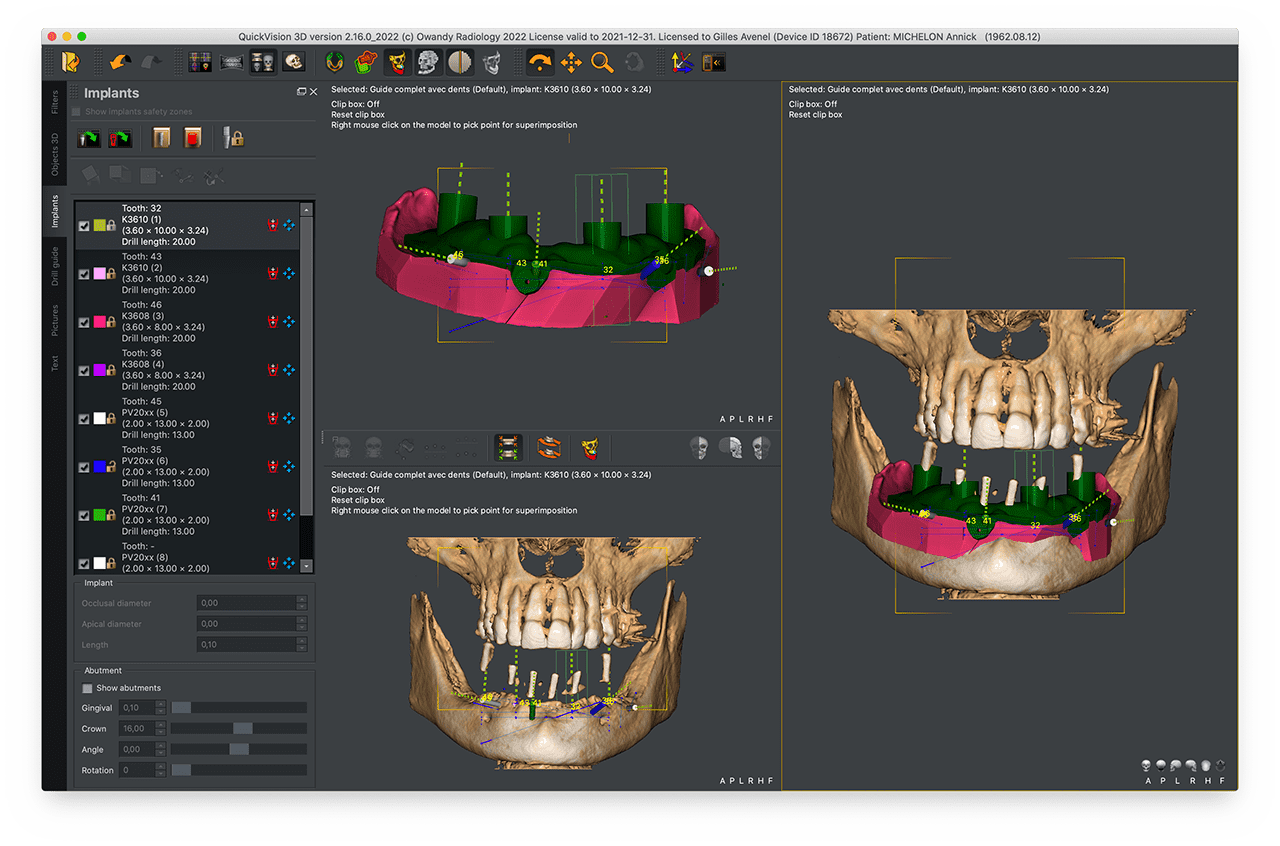

Quickvision 3D Creation of surgical guides

The primary purpose of this guide is to help the implantologist to preserve the anatomical structures of the jaws, but also to allow him to carry out immediate loading and aesthetics while being less invasive.

This innovative technique makes it possible to place dental implants using a digitally created guide and does not derogate from the basic rule of modern implantology where the prosthetic project controls the position of the implant and therefore the surgery.